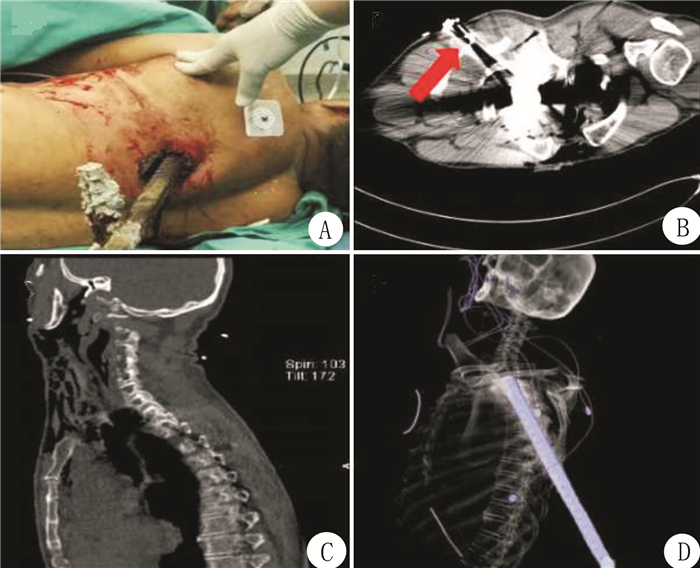

1 资料与方法患者,男,58岁,于2016年8月23日在建筑作业时不慎从2 m高处坠落,致左胸遭钢筋贯通伤,伤后呼吸困难,无昏迷,剪断末断钢筋后急送我院急诊科。查体:血压150/74 mmHg(1 mmHg=0.133 kPa),脉搏105次/min,R 24次/min,血氧饱和度88%,神清,面色及睑结膜苍白,俯卧位,左侧胸背5-6肋间处见外露钢筋(长约30 cm)(图 1A),部分进入胸腔,伤口出血不止,左肺可闻及湿啰音,右肺呼吸音粗,四肢活动尚可。血常规:WBC 24.58×109/L;NEU 75.4%;HGB 134 g/L;PLT 214×109/L。血生化:GLU 11.26 mmol/L;PT 13.5 s;APTT 29.4 s。其余正常。胸颈部CT示:左后胸壁至左肺尖部贯穿伤;左侧肩胛骨及第5~8肋骨多发骨折;左侧液气胸,部分为积血;左肺部分肺不张;左侧胸壁皮下气肿;颈部广泛皮下气肿;颈椎骨质平扫未见明显异常(图 1B)。诊断为“左胸部贯通伤;肋骨骨折;血气胸;肺损伤;血管神经损伤;失血性贫血。”

| 图 1 患者入院情况(A)和影像学检查结果(B、C、D) |

开放绿色通道,请胸外科、麻醉科等科室协同拟定抢救方案:急诊全麻下行左侧开胸探查术。术中见左后肋第4~9肋骨多根多处骨折,钢筋头端斜向前上方插入至左侧胸膜顶,壁层胸膜破损,直达左侧颈部皮下,钢筋紧贴主动脉弓向上刺破右头臂干动脉,左无名静脉破裂,左上肺组织可见一长约5 cm撕裂伤,术中取出钢筋,缝扎血管,修补肺组织,固定肋骨,术后转ICU病房监护。术后第2天撤呼吸机,第28天转康复科,第58天出院。除左肩及左上肢肌力未完全恢复外,其余恢复良好。